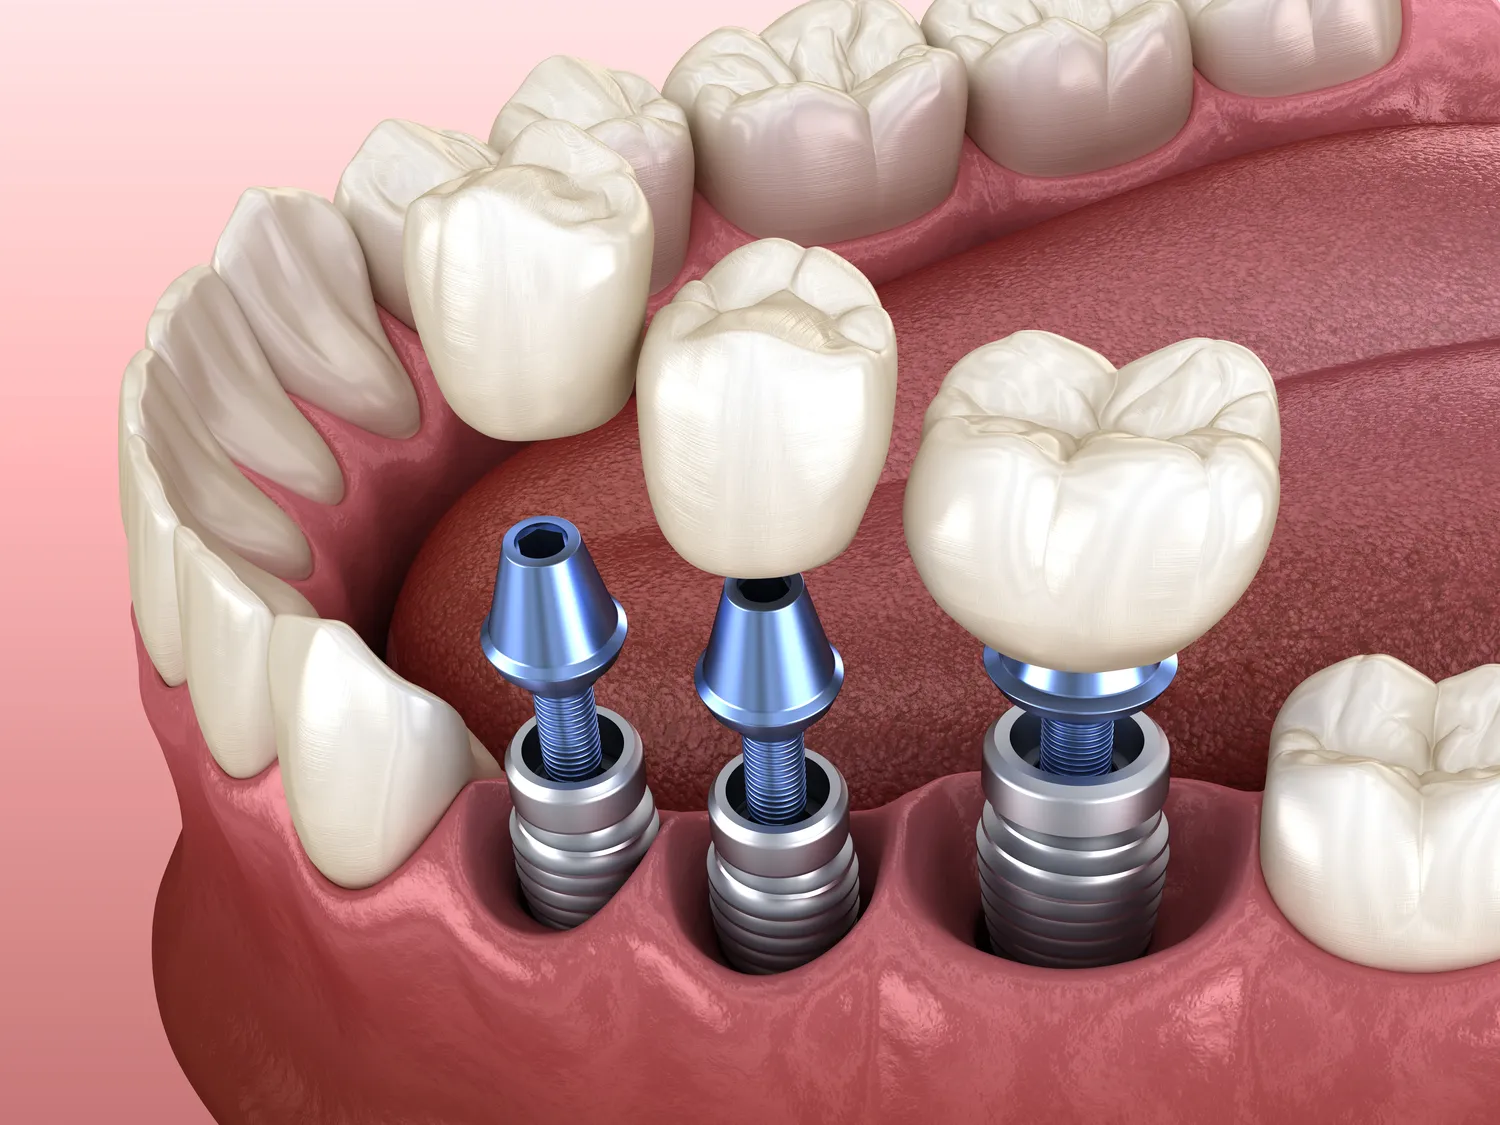

Różnice między implantami a protezami zębowymi są znaczące i mają wpływ na wybór odpowiedniego rozwiązania dla pacjenta. Implanty stomatologiczne to stałe rozwiązanie, które polega na wszczepieniu tytanowego słupa w kość szczęki, który następnie jest pokrywany koroną protetyczną. Dzięki temu implant działa jak naturalny korzeń zęba, co zapewnia stabilność oraz funkcjonalność. Z kolei protezy zębowe są ruchomym rozwiązaniem, które można łatwo wyjmować i zakładać. Protezy mogą być całkowite lub częściowe i często wymagają stosowania klejów do ich stabilizacji. W przypadku implantów nie ma potrzeby stosowania dodatkowych środków mocujących, co zwiększa komfort użytkowania. Kolejną różnicą jest trwałość; implanty przy odpowiedniej pielęgnacji mogą służyć przez wiele lat, podczas gdy protezy wymagają częstszej wymiany oraz dostosowywania do zmieniającej się struktury jamy ustnej.

Czas gojenia po wszczepieniu implantu może się różnić w zależności od wielu czynników, takich jak indywidualna reakcja organizmu pacjenta oraz jakość kości szczęki. Zwykle proces ten trwa od trzech do sześciu miesięcy; w tym czasie implant integruje się z kością w procesie zwanym osteointegracją. Jest to kluczowy etap, który decyduje o stabilności implantu i jego zdolności do pełnienia funkcji żucia. W przypadku pacjentów z dobrą jakością kości gojenie może przebiegać szybciej niż u osób z osłabioną strukturą kostną. Warto zaznaczyć, że podczas procesu gojenia pacjent może być zobowiązany do przestrzegania określonych zaleceń dotyczących diety oraz unikania nadmiernego obciążania miejsca wszczepienia implantu. Regularne wizyty kontrolne u dentysty są niezbędne do monitorowania postępu gojenia oraz ewentualnego wykrywania komplikacji na wczesnym etapie.